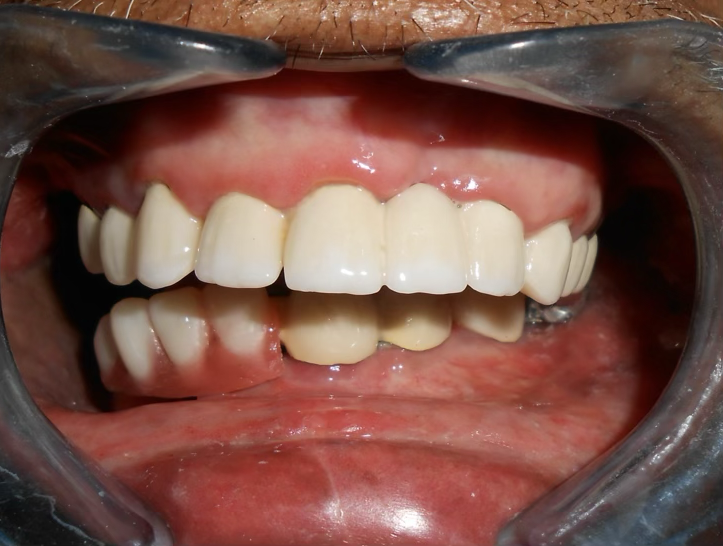

Final result

A 72-year-old male oral cancer survivor visited our dental center after surgical removal of the right side of his mandible. Patient had multiple missing and attrited teeth with significant functional impairment. Treatment involved implant-supported lower teeth with PFM crowns and precision-attached removable denture for hemimandibulectomy rehabilitation.

Implants were delayed loaded after 3 months with PFM crowns. Precision-attached metal removable denture was inserted for comprehensive hemimandibulectomy rehabilitation.